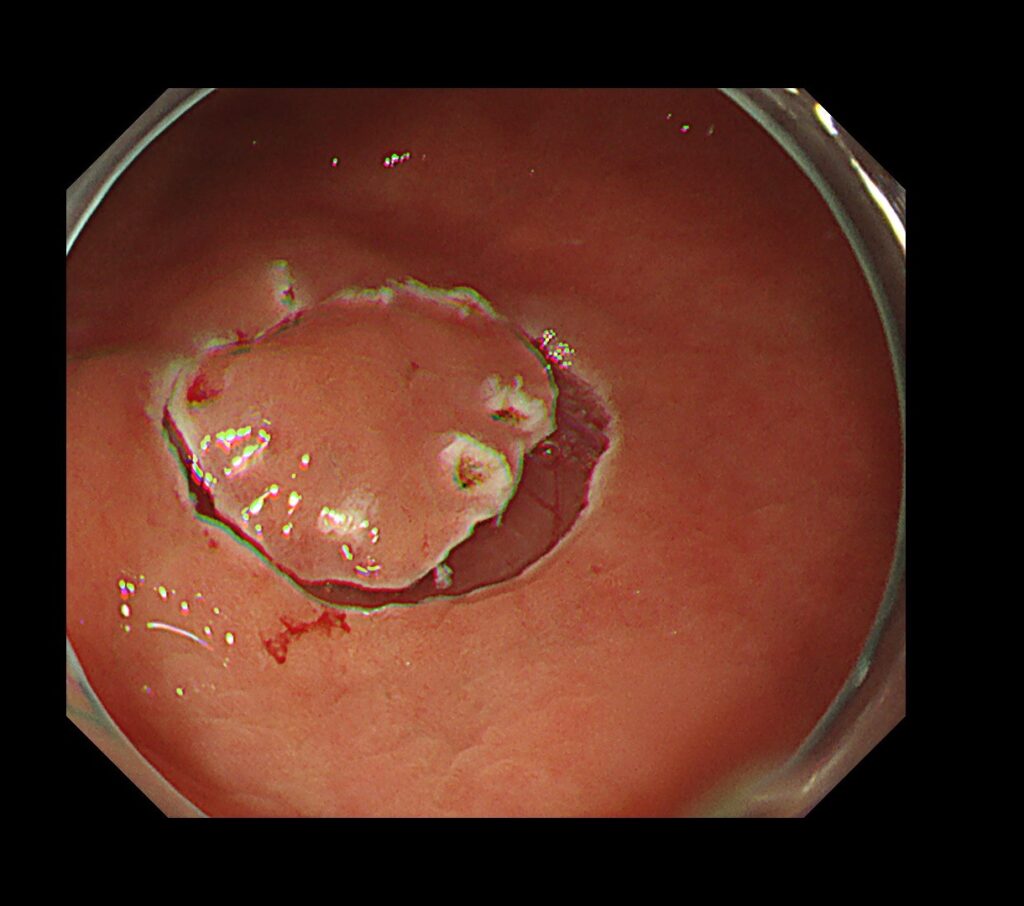

TXIモード(色と凹凸を強調するモード)にかえるとようやく、隠れていた胃癌が、画面中央に視認できるようになります。

私の得意分野であるNBIモード(癌の8割は茶色、周辺緑色)では、一目瞭然、TXIモードより、さらに癌の局在が明瞭化されます。

NBI拡大観察モード(倍率を上げて、癌の局在と範囲、組織型を確定させるモード)で、切除範囲をマーキングします。

マーキングから、病変摘出までわずか”3分”で終了。